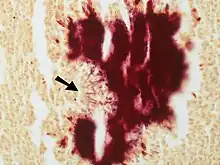

Contrast-enhanced magnetic resonance images showing contiguous spread of pulmonary actinomycosis to the spine -

Colony of Actinomyces surrounded by macrophages.. A Gram stain is needed to see the filamentous organisms. Large colonies of Actinomyces can appear macroscopically as yellow granules whch have been termed "sulfur granules". -